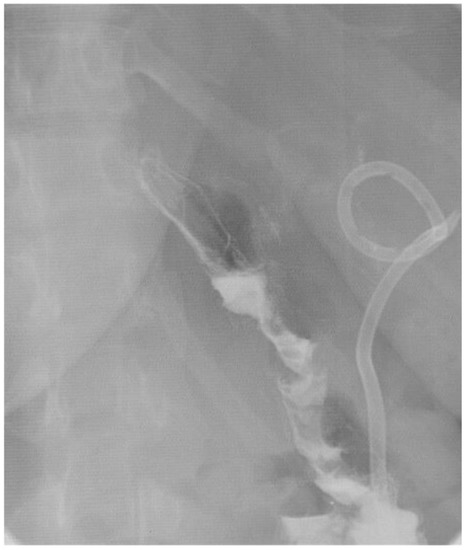

2. Detailed Case Description